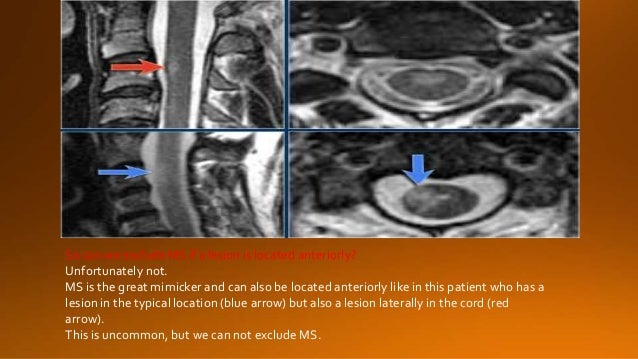

Reply